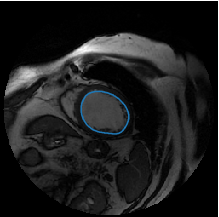

The Figure 1 below shows an example of an input image, the inferred region of interest (ROI), corresponding to the manually delineated contours.

From one original MRI image and its corresponding contour (provided as a list of coordinates of every point of the contour), we have to compute binary masks. We use the previous as inputs to our combined approach. An example is shown in Figure 2.